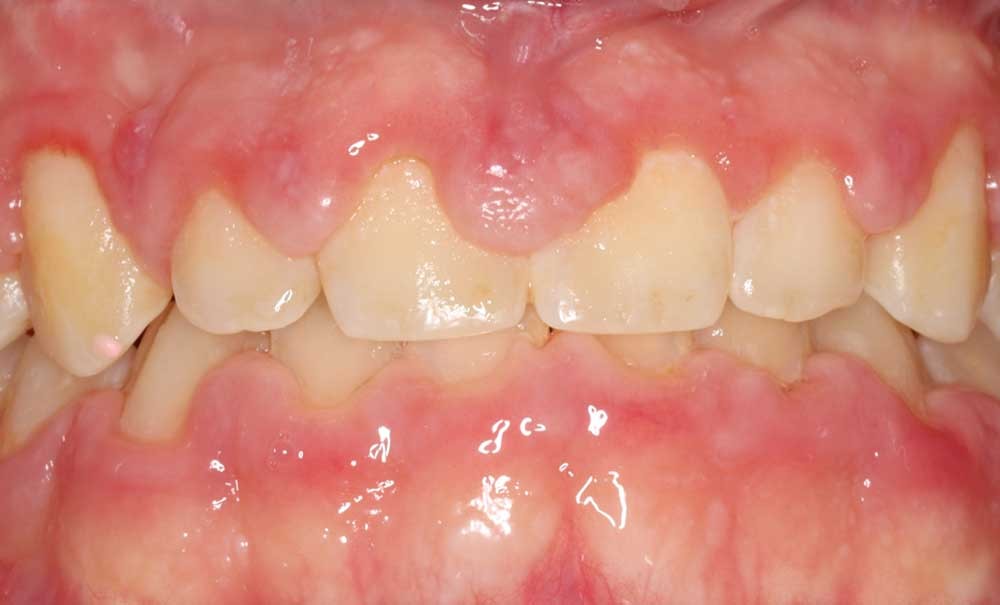

Le sourire dit « gingival » (ou classe 1 de Parodontia) est défini par la visibilité d’un bandeau continu de gencive supérieur à 3 mm [1]. L’éruption passive incomplète [2] est connue comme l’une des étiologies du sourire gingival en modifiant l’harmonie dento-faciale : les dents présentent une forme carrée et l’excès de gencive visible donne un sourire gingival prononcé. Une procédure de chirurgie plastique soustractive [3] permettra d’améliorer l’esthétique globale du sourire en rétablissant des volumes et des formes harmonieuses des dents et du parodonte. Très souvent, à côté de la redéfinition des contours gingivaux en excès par gingivectomie, il sera nécessaire de procéder à un remodelage osseux pour rétablir l’attache supra-crestale (espace biologique) [4]. Cette procédure d’élongation coronaire soulève de nombreuses questions quant aux paramètres à analyser, à la quantité d’os à enlever, au matériel à utiliser, au positionnement du lambeau par rapport à la crête osseuse et aux délais de cicatrisation.

Lorsque l’éruption passive ne se produit pas ou s’interrompt, la gencive demeure en position coronaire et recouvre une quantité trop importante d’émail : on parle alors d’éruption passive altérée, retardée ou incomplète. Coslet et al. ont classé l’éruption passive altérée en deux types fondés sur la hauteur de tissu kératinisé, et en deux sous-groupes basés sur la position de la crête osseuse alvéolaire par rapport à la jonction amélo-cémentaire [7].

Un excès de tissu gingival peut interférer avec une hygiène bucco-dentaire adéquate et l’accumulation de plaque peut provoquer une inflammation gingivale marginale [9]. De plus, les restaurations et appareils orthodontiques placés à proximité de la gencive marginale peuvent provoquer une réponse inflammatoire entraînant une gingivite et parfois une perte d’attache. D’autres facteurs comme des traumatismes causés par le frottement des aliments ou la respiration buccale peuvent contribuer à l’inflammation chronique de la gencive.